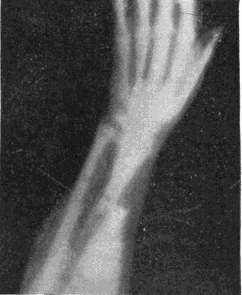

Fig. 4.—Knee, Knickerbocker Buttons, Bullet in Femur.